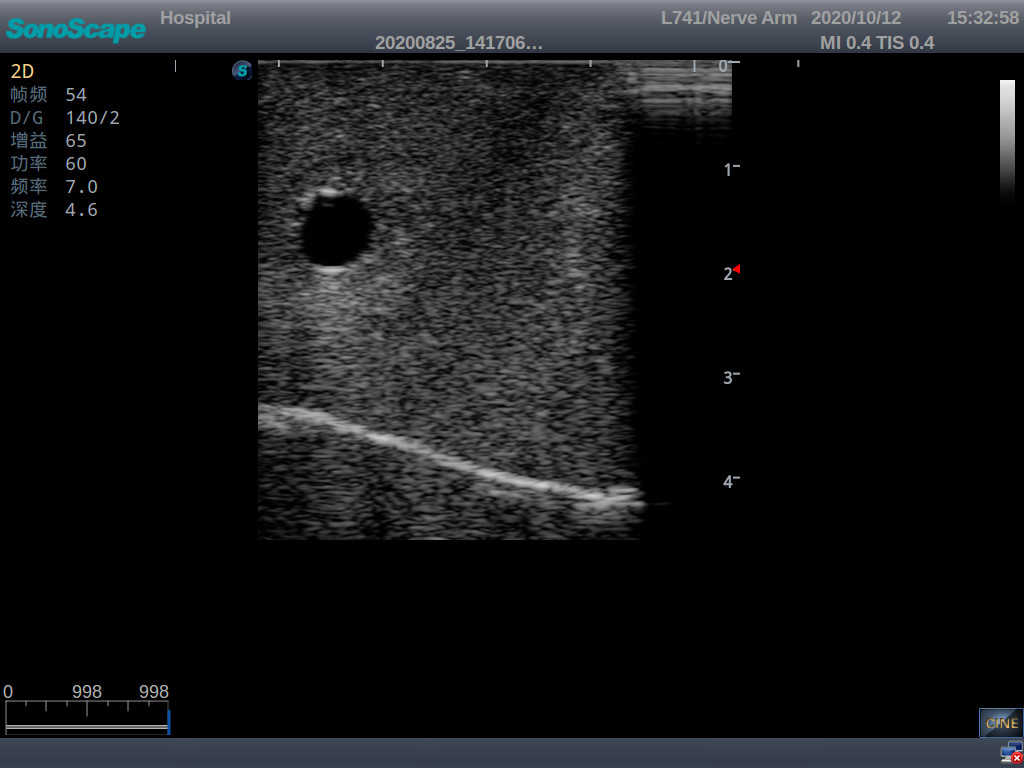

Central Venous Catheterization Ultrasound Training Model

Model TYE1510.2

Product size(mm)700×500×160

Outline

It is a model from the earlobe plane to the umbilical plane with its head turned to one side. It's put in a standard central venipucture and catheterization position, including landmarks such as right arm, clavicle, ribs, sternocleidomastoid muscle, sternoclavicular joint, etc. It can be used for ultrasound-guided subclavian vein and internal jugular vein puncture and catheterization. The model's arm can be used for ultrasound-guided PICC catheter placement.

Skills Gained

· Subclavian vein puncture and catheterization

· Internal jugular vein puncture and catheterization

· PICC catheter placement

Features

· Anatomy:

Right internal jugular vein, right common carotid artery, superior vena cava, right brachiocephalic vein, right brachiocephalic trunk, right subclavian vein, right subclavian artery, etc.

· Key Features:

1)  The module for central venous catheterization is transparent, allowing users to clearly see the course and adjacent relationship of blood vessels

2)  The puncture module supports using a clinical real ultrasound machine to observe clear images such as right internal jugular vein, right common carotid artery, superior vena cava, right brachiocephalic vein, right brachiocephalic trunk, right subclavian vein, right subclavian artery, etc.

3)  The puncture pad at the arm is made of high-molecular ultrasound material, close to real skin. It can support the use of real ultrasound machines, and the images of tissue structures (skin, subcutaneous tissue, blood vessels) under ultrasound are clear and real

4)  A sense of “pop” can be felt when the vascular puncture is successful, and the outflow of venous blood can be simulated

5)  The guide wire’s march can be observed under the guidance of ultrasound, and also whether the catheter is placed correctly can be detected

6)   All the puncture modules are replaceable